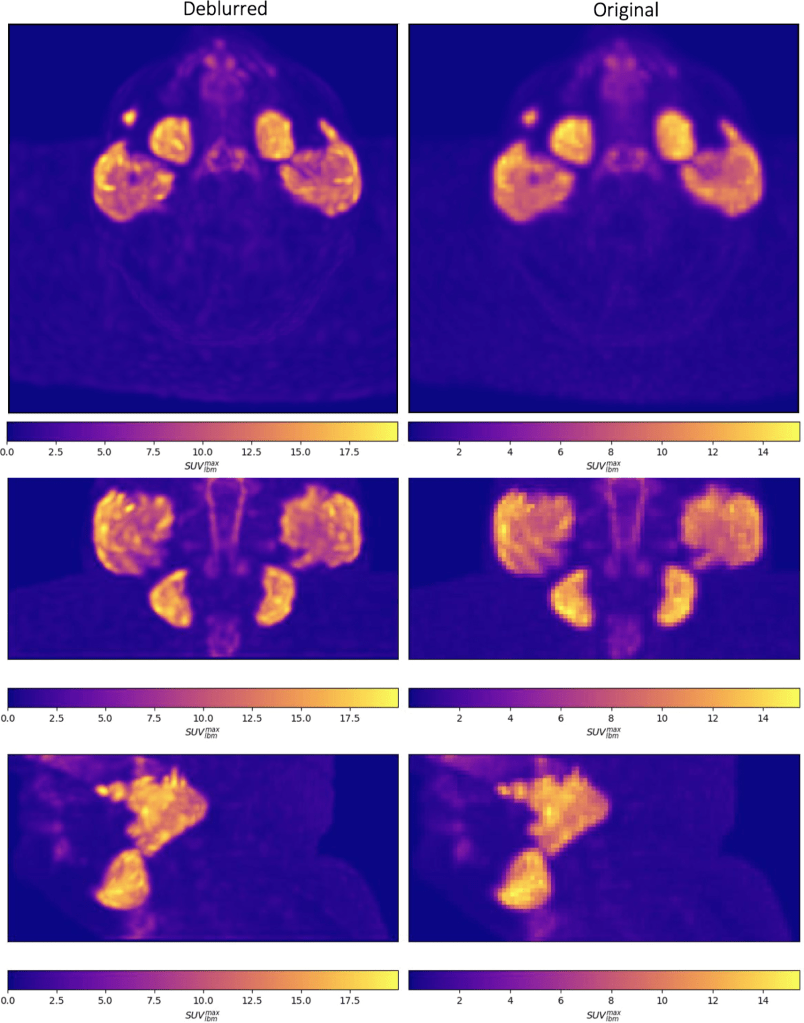

Visual comparisons of original and deblurred PET image slices including parotid glands and submandibular glands are shown for 3 different patients in figure below

Axial slices intersecting parotid glands (left) and submandibular glands (right) for 3 different patients are shown on original and deblurred images